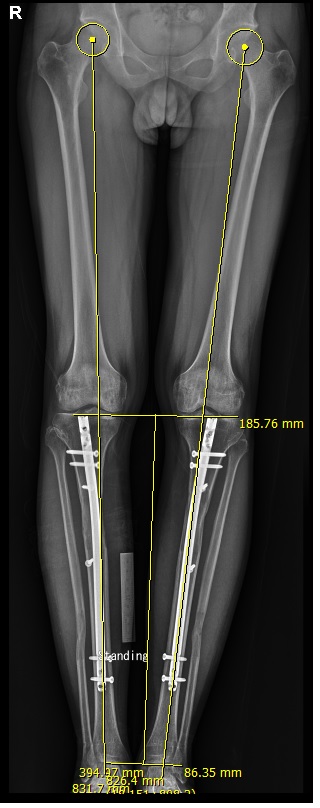

아래 사진을 보면, 수술전 종아리의 길이는 실제로 331mm로 측정되는데, 이는 영상 보정을 옆의 금속자 10cm를 기준으로 보정한 상태이며, 수술 후 종아리의 길이는 실제로 395mm로 64mm의 연장이 된 상태이다. 수술 후 사진에서 10cm 금속자를 이용해서 보정한 사진이다. 실제 이 환자의 척추 사진인데 측만증이 흉요추부에 있어 키 측정에서 오차를 나타낼 수 있다.

즉 다리는 길어지지만, 상체에서 차이가 측정 시마다 시기마다, 시간이 지날수록 차이를 나타낼 수있다.

종아리 속성 연장 수술 환자의 수술 전후 엑스레이 사진으로 종아리 길이가 영상 보정 후 331mm에서 395mm로 측정된다. 64mm 연장 사진으로 6.4cm 연장된 사진이며, 이는 실측과 오차가 없다고 생각할 수 있다.